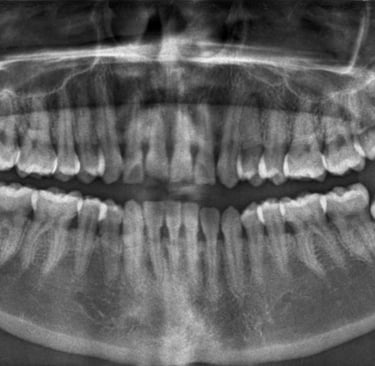

Son muy útiles para detectar fracturas, infecciones, problemas pulmonares o dentales, entre otros.